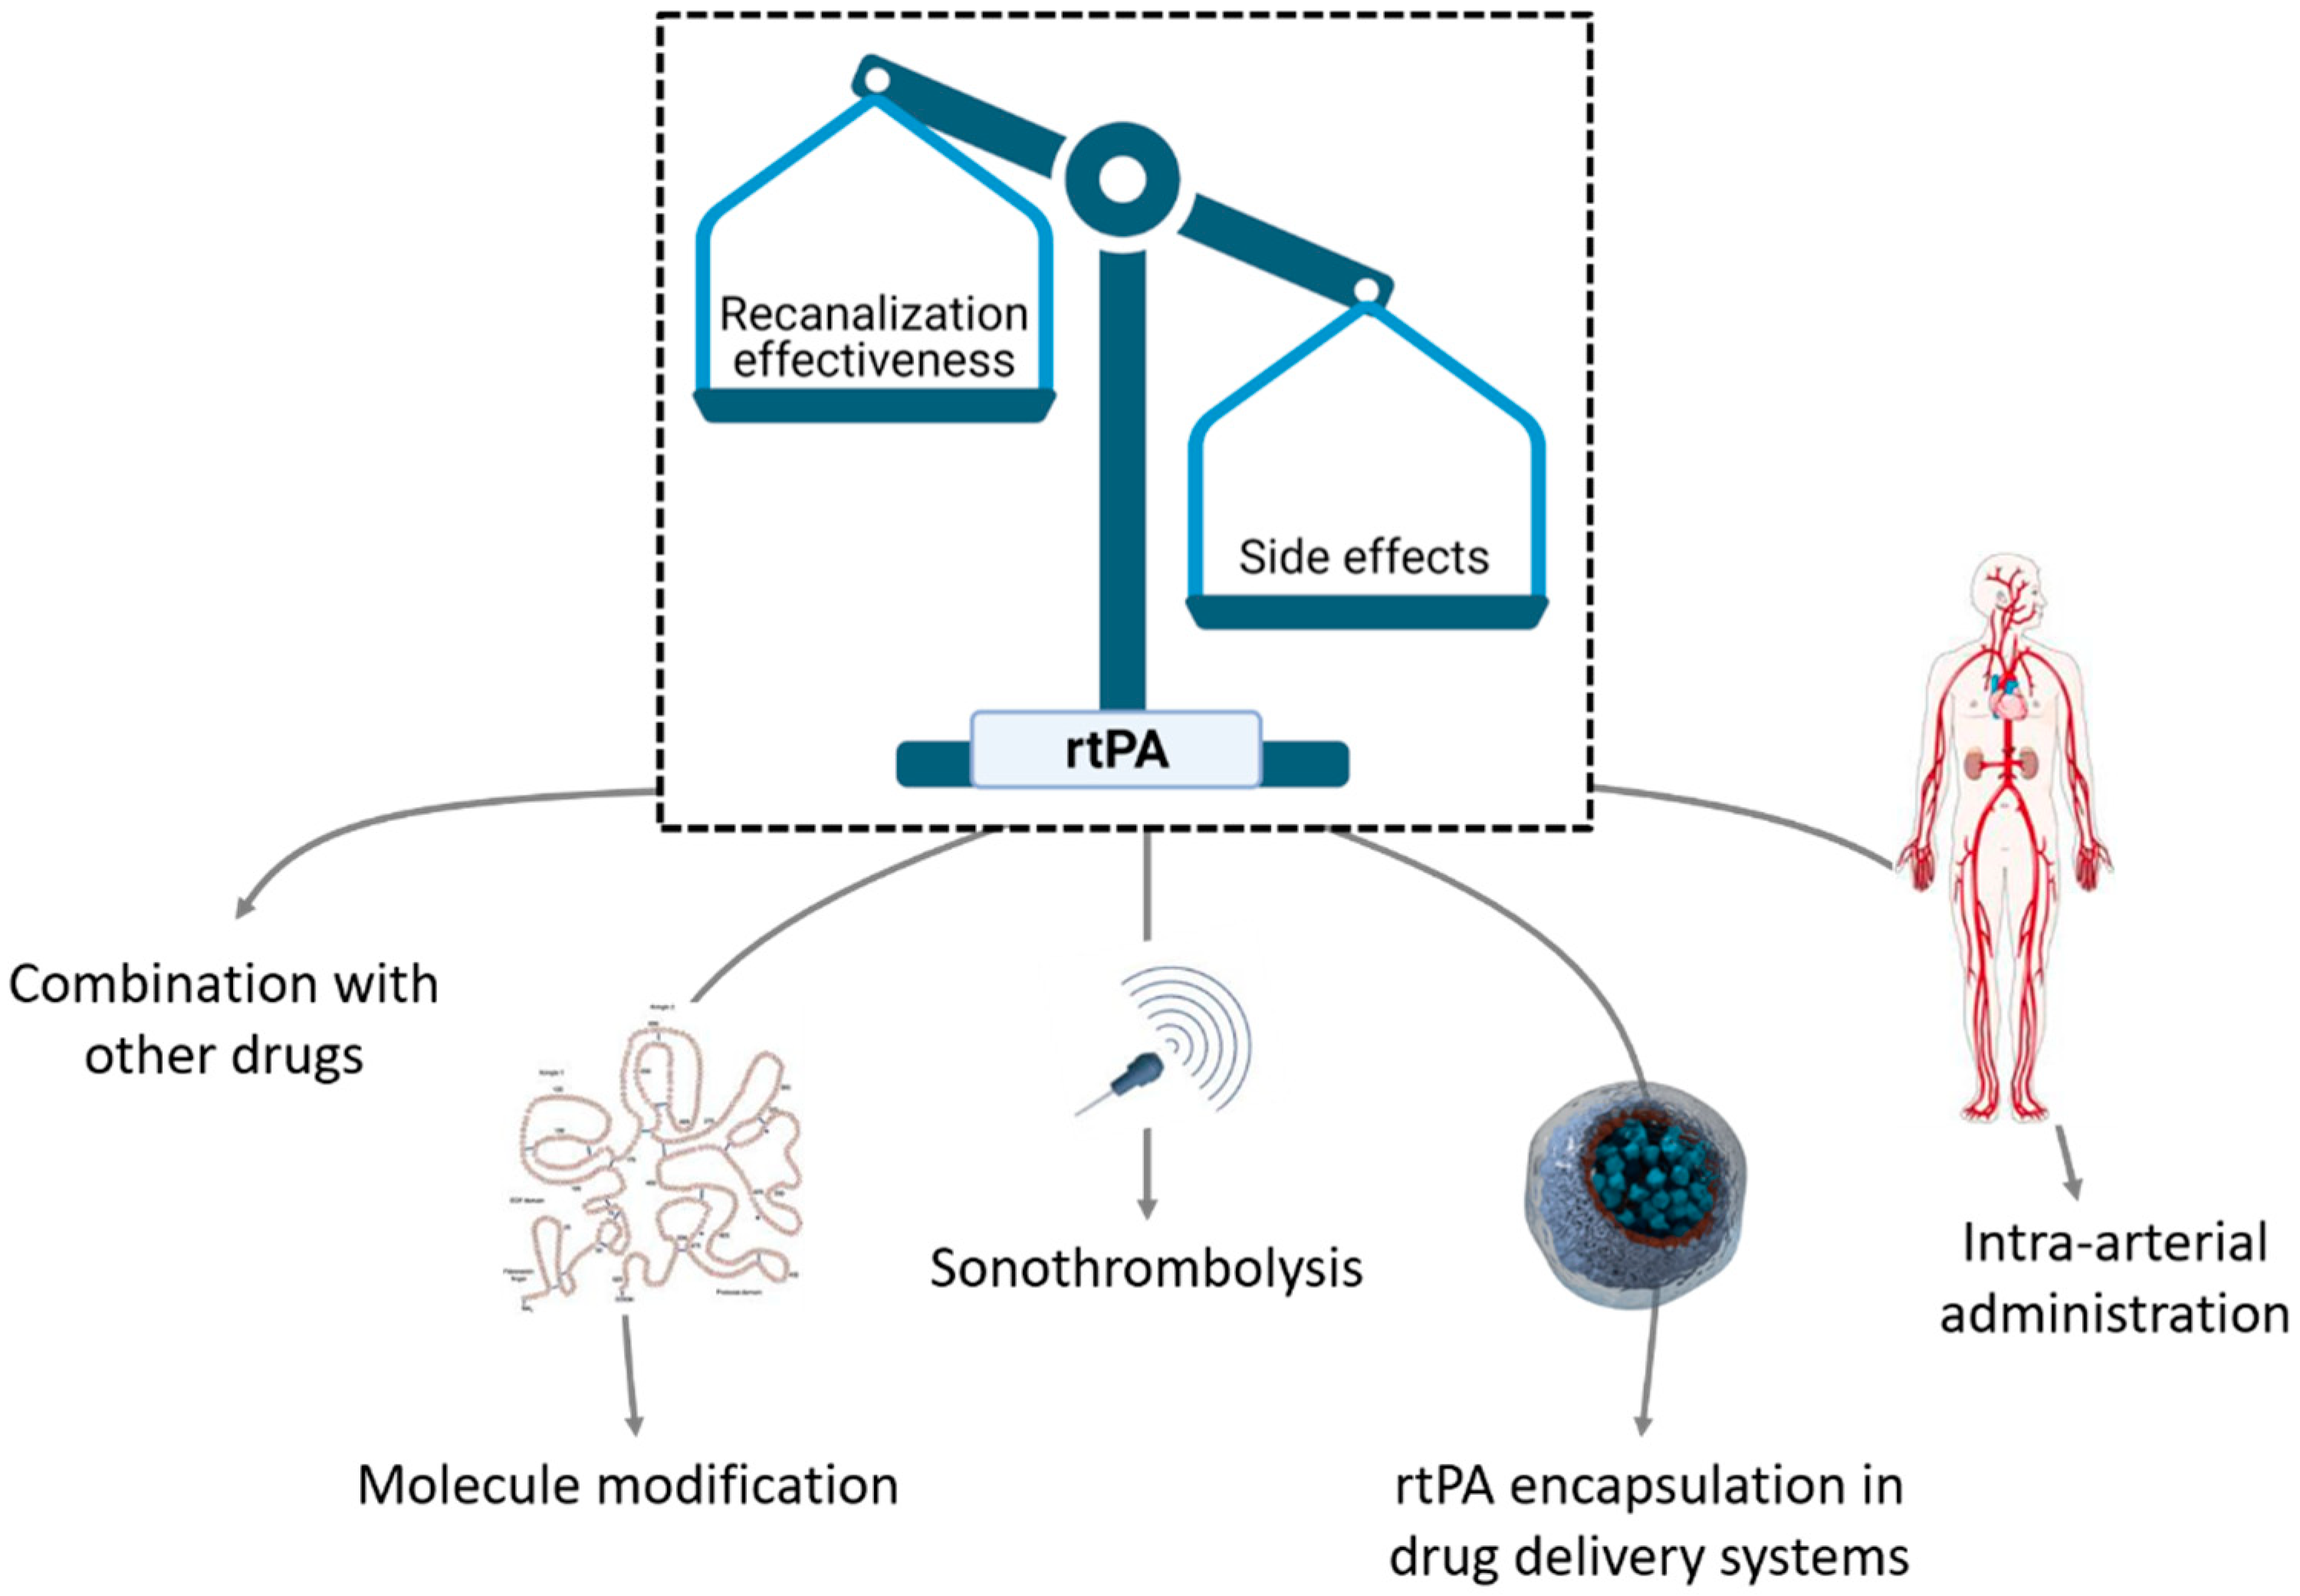

3.1. Nanocarriers for rtPA